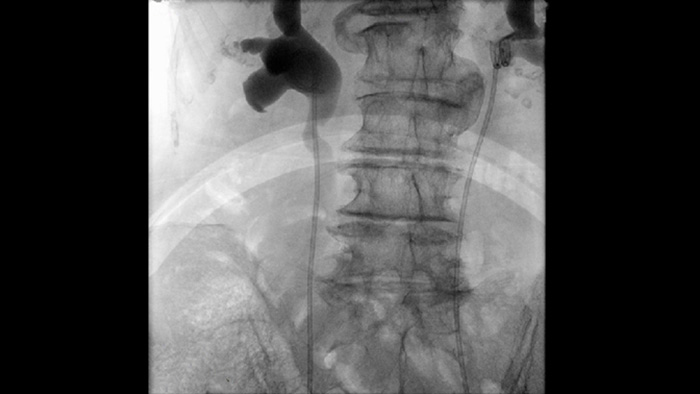

La fluoroscopia pulsada mejora las imágenes de las características anatómicas densas y complejas para ayudarle en el manejo de la dosis. Puede seleccionar un rango de frecuencias de pulsos de fluoroscopia para reducir la dosis cuando se desee o mejorar la calidad de la imagen según sea necesario.

Los parámetros de imágenes predefinidos para diferentes procedimientos y características anatómicas, que se pueden personalizar por aplicación, aumentan la confianza clínica y la eficiencia para los diversos procedimientos y pacientes de cada día.